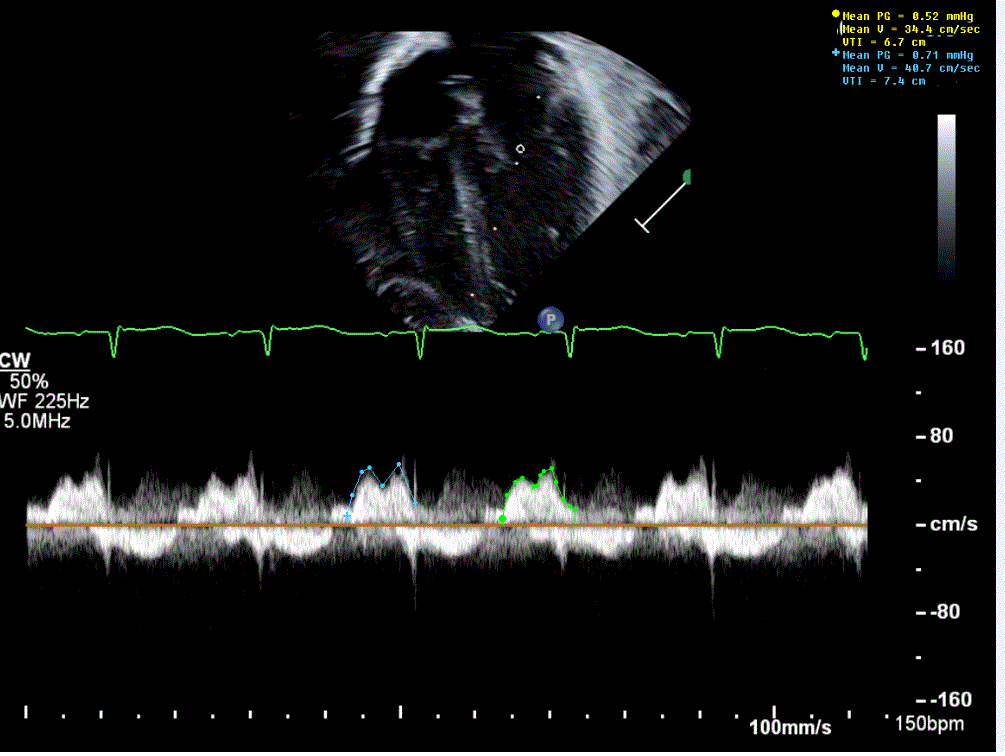

What is Wrong

Depth too shallow, need to decrease Depth so TAPSE is not running through EKG